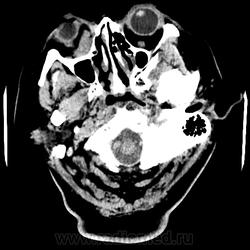

Женщина 48 лет, поступила с подозрением не ОНМК. На КТ -данных за ОНМК не обнаружено, но в правой орбите ретробульбарно мягкотканное образование +45HU, признаков деструкции и ремоделирования костных структур орбиты не наблюдается, медиальная и нижняя прямая мышца отчетливо не дифференцируются, зрительный нерв тесно прилежит к данному образованию. После КУ гомогенное накопление КВ и повышение плотности до +65HU. Экзофтальм. Жалобы на снижение зрения. Год назад делала МРТ ГМ, на снимке патологии орбит не увидел. Идиопатическая псевдоопухоль орбиты?

В мягких тканях носогубного треугольника справа тоже образование.

Контраст